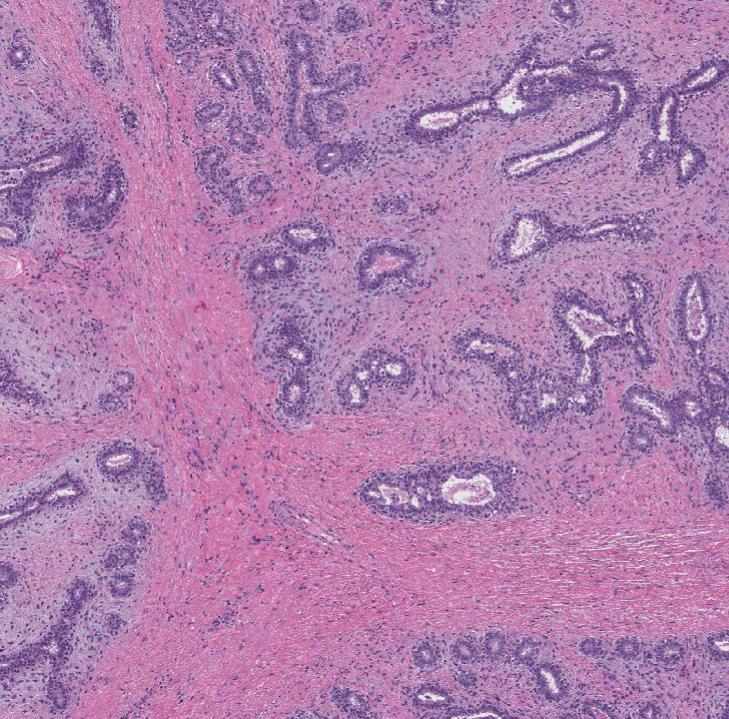

Классическая гистологическая картина фиброаденомы: железистые трубочки ("дырочки") и разросшаяся строма (сероватые участки вокруг трубочек).